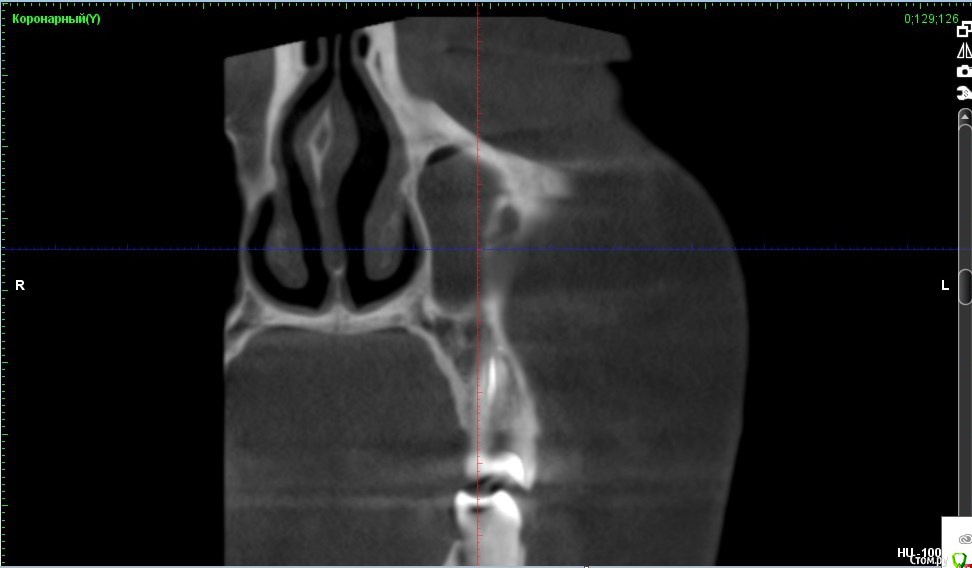

Verasss Опубликовано 8 октября, 2016 Автор Поделиться Опубликовано 8 октября, 2016 КТ от 08.09. Извините, что в таком виде, надо менять ОЗУ. Ссылка на комментарий

Verasss Опубликовано 28 октября, 2016 Автор Поделиться Опубликовано 28 октября, 2016 Добрый вечер! Ещё раз попытаюсь прикрепить скриншоты КТ от сентября. Если качество совсем не устраивает, подскажите, пожалуйста, какие сделать снимки?К сожалению, программа не позволяет вывести снимки на полный экран и заскриншотить в более хорошем качестве. Ссылка на комментарий

Verasss Опубликовано 28 октября, 2016 Автор Поделиться Опубликовано 28 октября, 2016 еще снимки Ссылка на комментарий

Verasss Опубликовано 28 октября, 2016 Автор Поделиться Опубликовано 28 октября, 2016 и еще Ссылка на комментарий

DmitrySH Опубликовано 8 октября, 2016 Поделиться Опубликовано 8 октября, 2016 В таком виде КТ малоинформативно. Но гайморита нет. Ссылка на комментарий